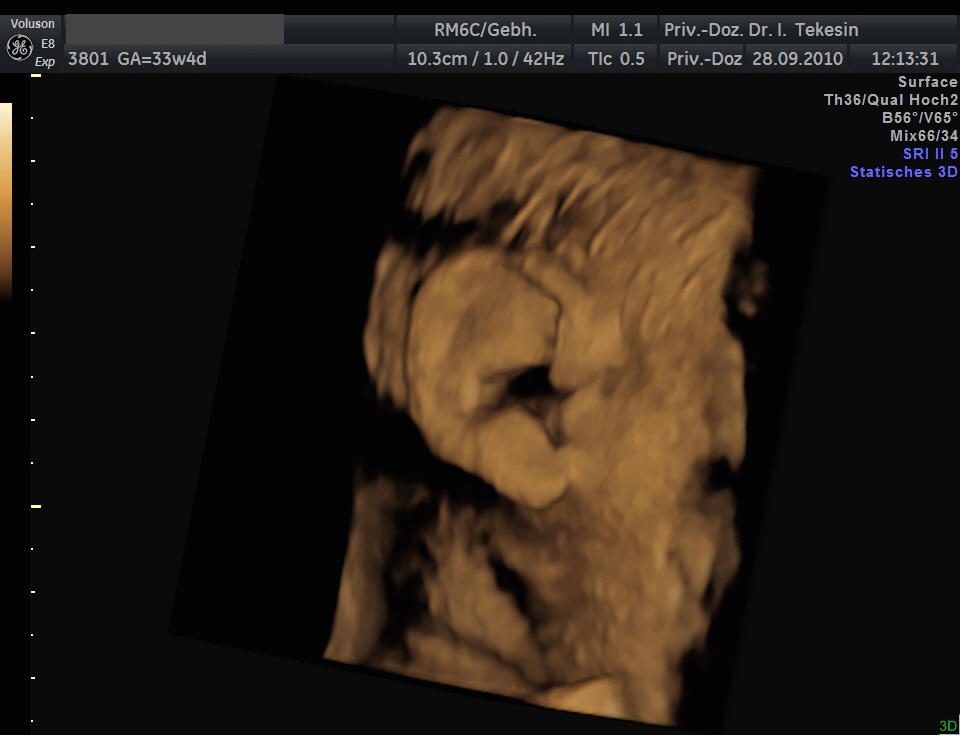

Ohr und Haare in der 34. Woche (3D-Darstellung)